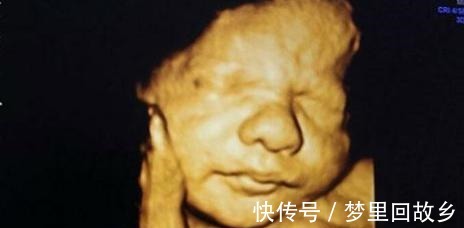

先天|孕检很正常,却生下畸形儿,医生这5种情况四维彩超也看不出

优优的体质属于难孕型,所以球球是她和老公备孕了将近3年才怀上的,人家可能只过了10个月的孕期日子,但她这三年多以来,为了能够怀上小家伙,饮食与行为都极为注意。后来怀上球球之后,优优更加小心了,她的每次产检都有按规定去做。而且在整个孕期中做了12次产检,额外还有四次B超与一次四维,没有一次的结果是不正常的。所以这一直是优优想不明白的地方,后来医生和她说,四维的作用虽是排畸,但这下面几种畸变并不能完全检查出来。【 先天|孕检很正常,却生下畸形儿,医生这5种情况四维彩超也看不出】

1、全盲虽然四维可以看到小家伙清晰的五官,但胎宝的眼睛都是闭着的,因为腹内没有光线刺激,所以通常情况下,小家伙都不会睁开眼睛。所以他们的视力情况是无法准确检查出来的,这也就导致有些先天全盲或是小眼症的状况不能被发现。2、水肾与水脑一般来说,水肾与水脑的情况要到孕后期才会出现,而这一情况四维也无法完全检查出来。

3、先天听力障碍这点和视力有些相像,而小家伙在5~6个月的时候,听力就发育完全了,所以很多孕妈妈会在这时进行音乐、沟通等胎教法,但这样并不能察觉小家伙的听力是否有问题,而且也没有其他方法可以检查出听力异常的情况。4、先天心脏疾病小家伙的心房以及动静脉的导管在出生后都会关闭,所以心脏是否有问题在刚出生时是可以诊断出来的,但在胎中无法检测。

5、手指或脚趾异常有些胎宝在出宫后才发现脚趾或是手指有畸变情况,所以就会责怪医院方面没有检查清楚,有些家长甚至走了法律途径,但四维对这一情况确实不能准备给出判断。因为小家伙宫内的状态,基本都是呈握拳状态的,所以超音波也无法探测其是否有畸变。所以,孕妈妈们可别觉得每一次的产检都正常就可以放肆了,就连优优那般谨慎都出现那样的后果。可见,想孕育出一个健康且健全的娃娃并不容易,孕妈妈们在孕期内一定要谨慎再谨慎!